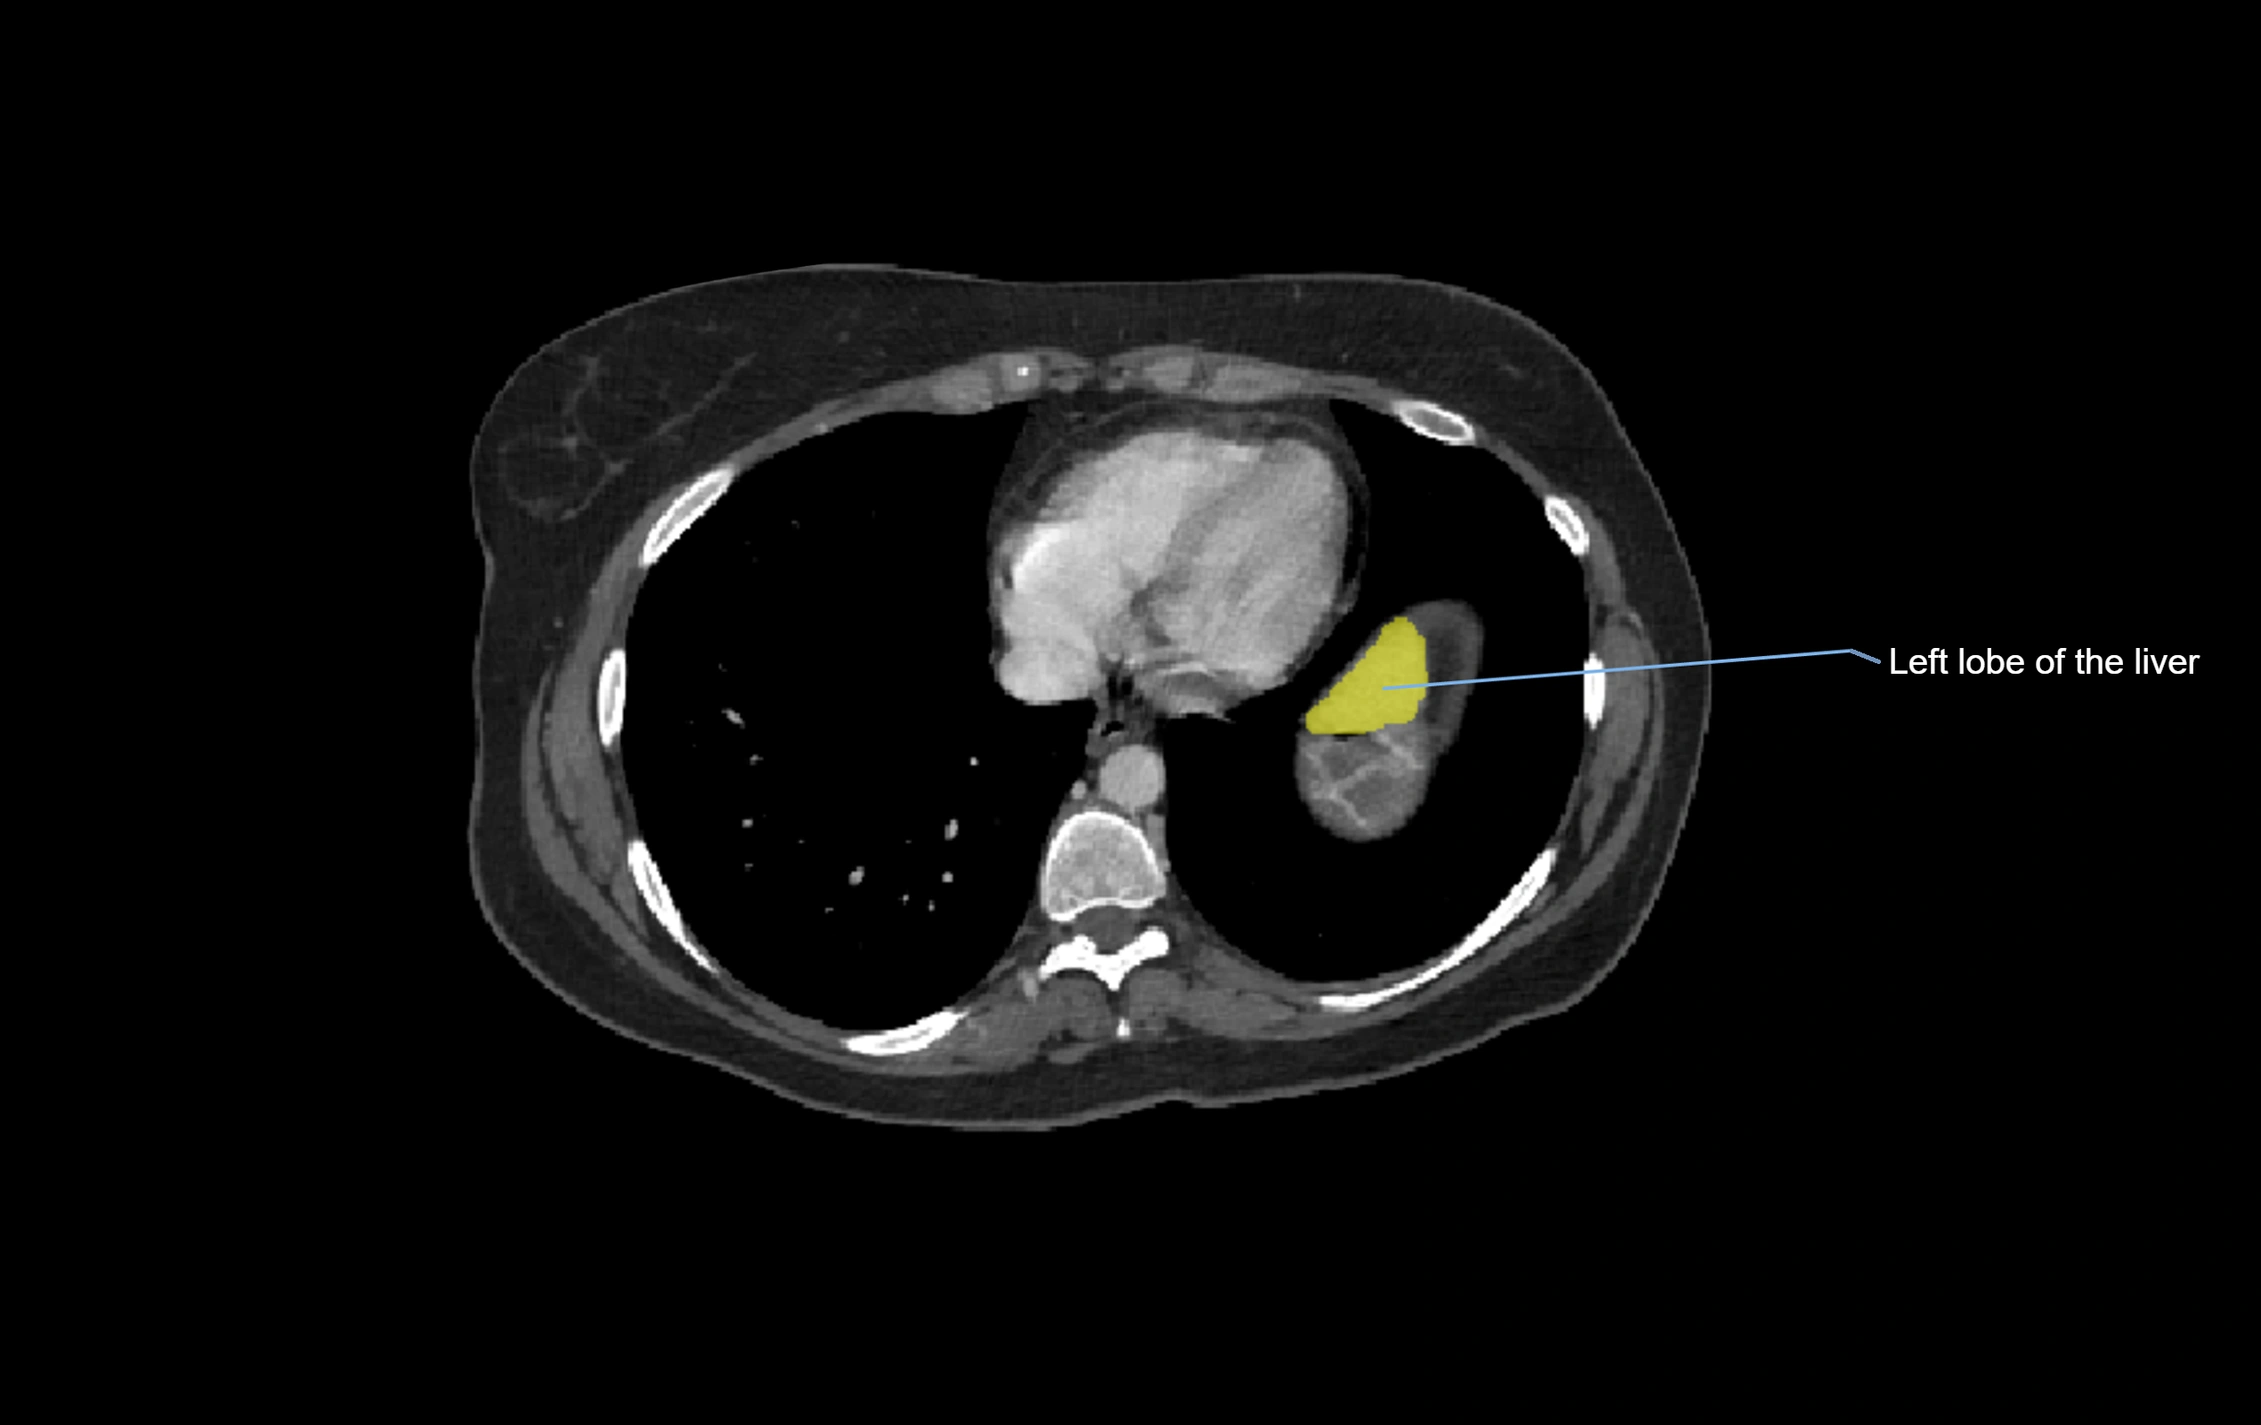

CT Image

image